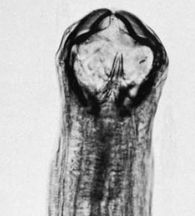

アメリカ鉤虫:ネカトール・アメリカヌス(Necator americanus)、頭端は背方に曲がり、口腔は球形に近く、切板は半月形です。Ancylostoma属のものより小形で、雄7~10mm、雌9~13mm

ヒトまれに犬、猫、豚の小腸に寄生し、熱帯・亜熱帯地方、特にアメリカとアフリカに多く、本邦にも分布します。